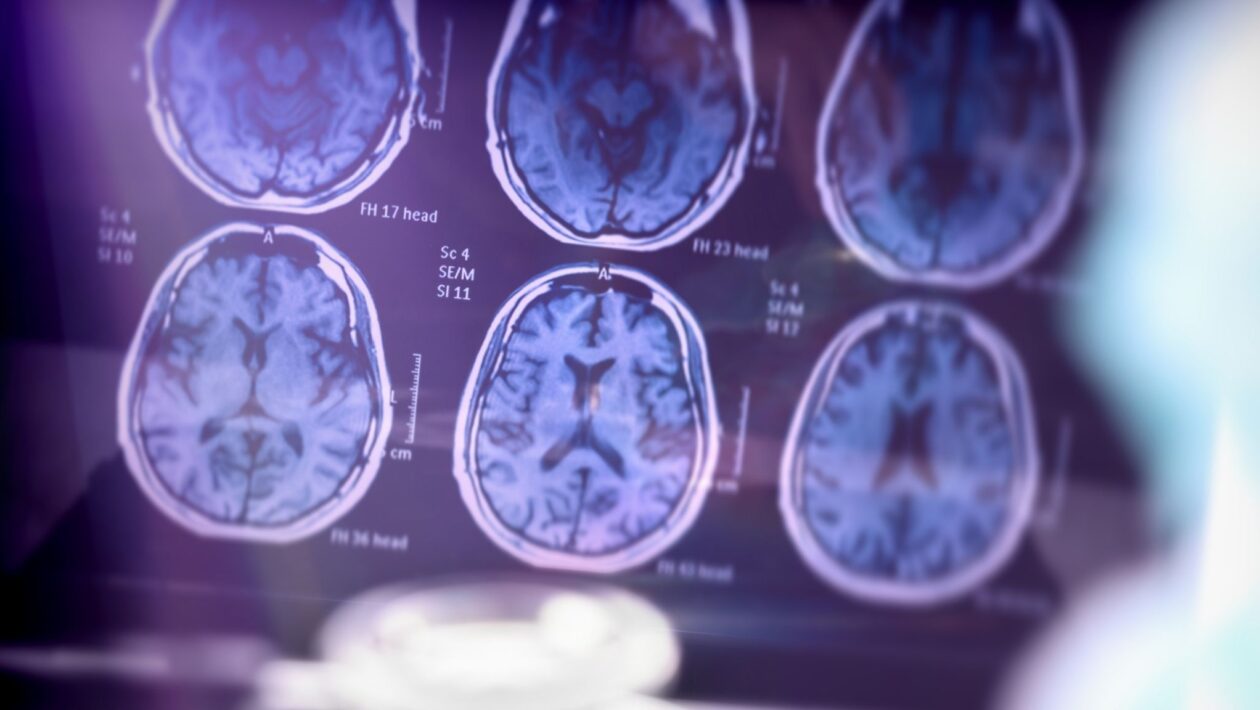

A IA comparou os exames com um banco de dados de mais de 3.600 imagens cerebrais, reconhecendo padrões típicos de doenças como Alzheimer, demência por corpos de Lewy e demência frontotemporal.

Um dos diferenciais da tecnologia é a geração de mapas digitais coloridos que destacam as áreas do cérebro comprometidas, facilitando a análise mesmo para médicos que não são especialistas. Além disso, os exames puderam ser interpretados quase duas vezes mais rápido em comparação ao método tradicional.